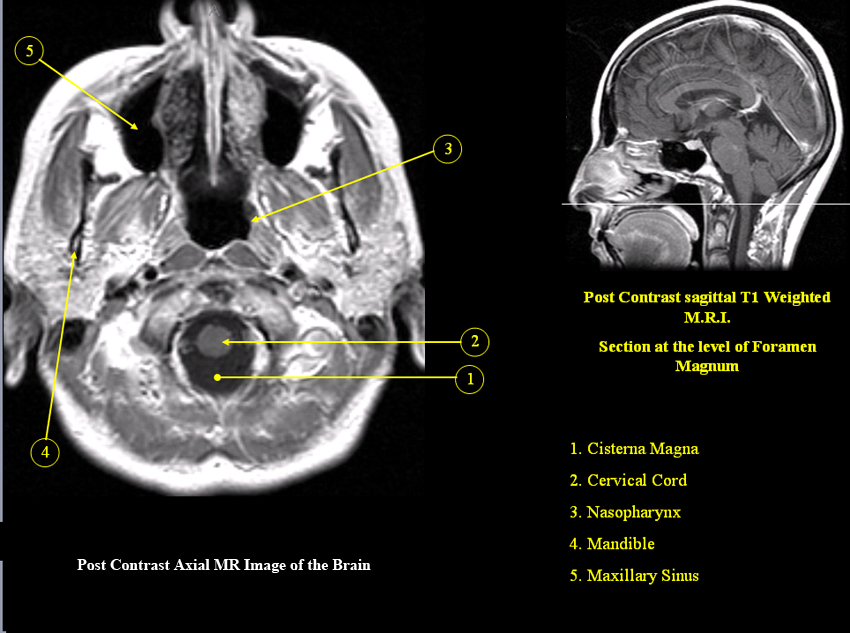

MR Brain and Spine